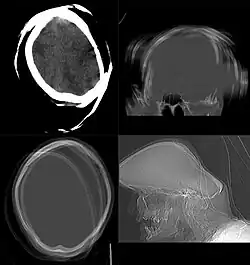

CT scan remains the cornerstone imaging modality for the initial evaluation and subsequent management of patients with acute traumatic brain injury due to its rapid acquisition time and high sensitivity for detecting hemorrhagic complications, such as intraparenchymal hematomas and subdural hemorrhages.[56] CT scan of the head is typically used to detect infarction (stroke), tumors, calcifications, haemorrhage.[57] Tumors can be detected by the swelling and anatomical distortion they cause, or by surrounding edema. CT scanning of the head is also used in CT-guided stereotactic surgery and radiosurgery for treatment of intracranial tumors, arteriovenous malformations, and other surgically treatable conditions using a device known as the N-localizer.[58][59][60][61][62][63]

Non-contrast CT

CT procedure in which contrast media is not used is often called as Non-Contrast CT (NCCT) or plain CT. This procedure is employed when there is already a sufficient contrast distinction in the target tissues, rendering the resulting image diagnostically significant. The process involves acquiring a topogram, followed by scanning the region of interest and reconstructing the data, marking the conclusion of the procedure. The non-contrast CT scans are rapid, less hazardous, and cost-effective procedures. Non-contrast CT head scans are useful in the identification of various conditions, encompassing traumatic hemorrhages, subdural hematomas, cerebral edema, fractures, and in detecting foreign bodies, such as tempered glass, in emergency situation.[134]